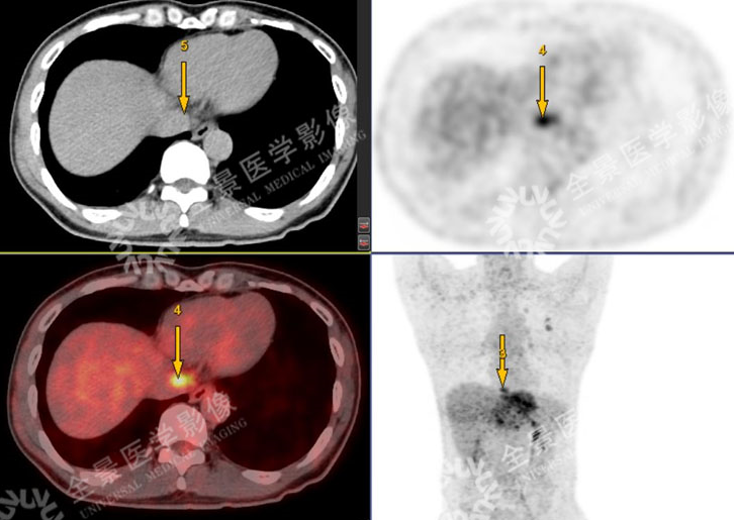

男性,57岁,上腹疼痛2月余,加重1周。外院CT:肝左叶占位。既往有乙肝病史多年。

SUVmax=4.59

PET示:腔静脉裂孔处结节FDG摄取增高;

CT示:无明显异常密度影。

怀疑:腔静脉癌栓?后心膈角区淋巴结?

确诊:腔静脉癌栓